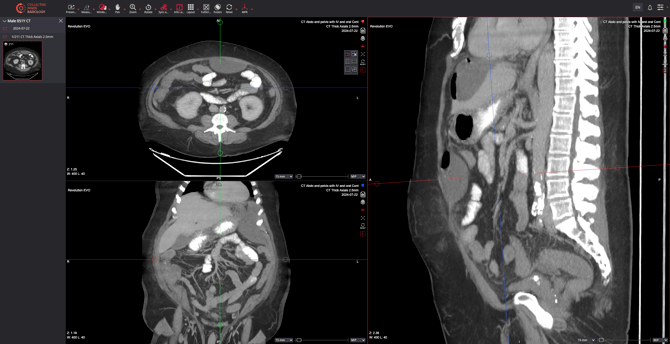

The MPR feature allows custom cross-sectional views to be made at any angle and apply projection modes like MIP, MinIP, and Average.

- Navigate to the toolbar menu and select MPR > MIST Oblique

- Manipulate crosshairs: Drag, angle, or rotate the crosshairs to adjust the image plane orientation. This enables cross-sectional views at any angle.

- Set slice thickness: Adjust using the slide bar or select from the menu at the bottom of the viewport.

- Maximum Intensity Projection (MIP): Displays the highest intensity values in the dataset. Ideal for vascular imaging, such as CT angiography.

Minimum Intensity Projection (MinIP): Highlights the lowest intensity values, useful for air-filled structures like the lungs.- Average Projection (AVG): Computes the average intensity across a defined plane thickness, offering a balanced view of tissue densities.